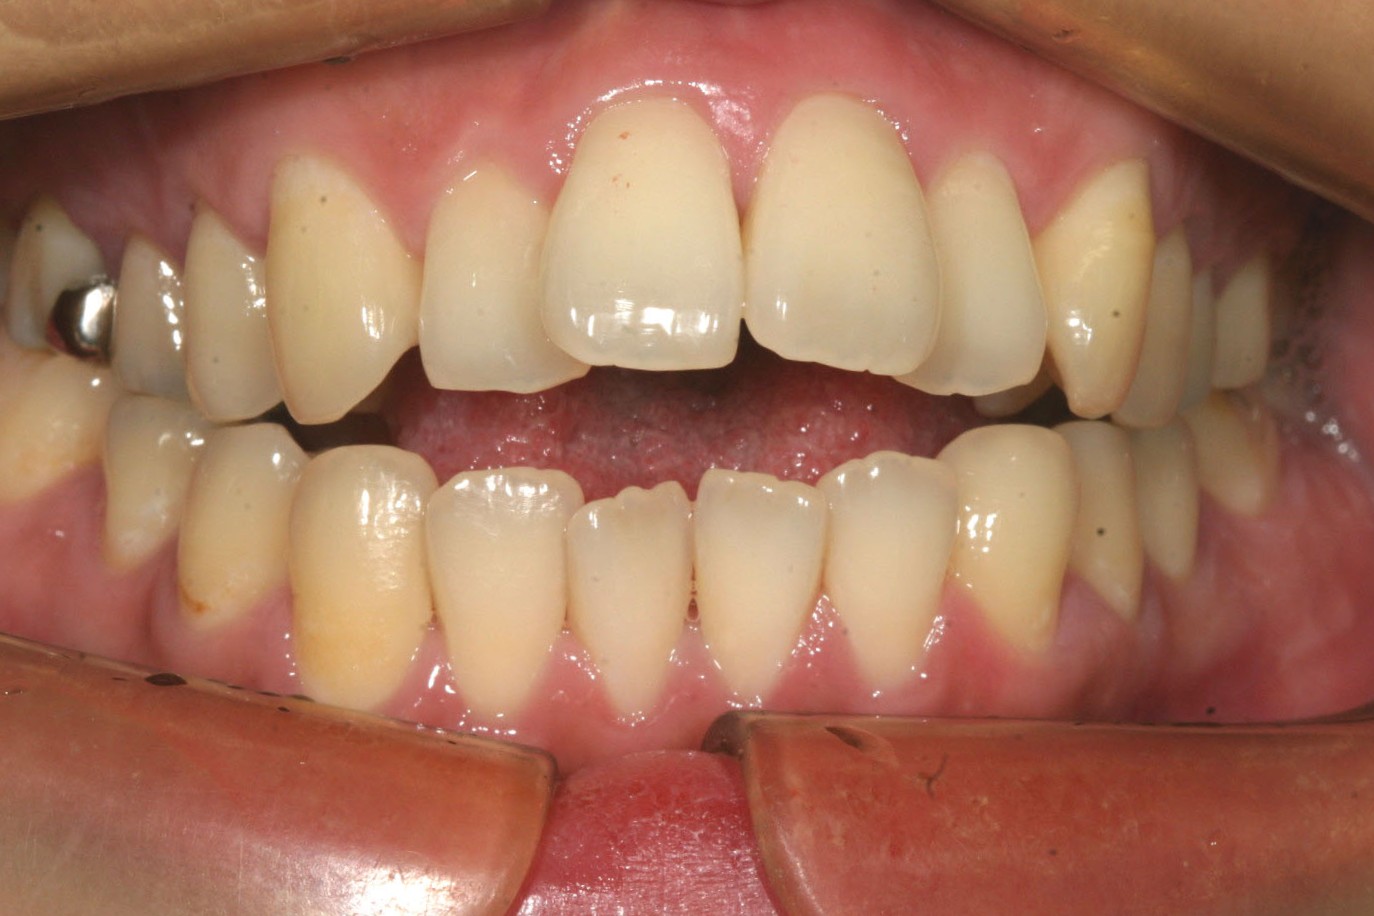

側面観も上顎が出て開咬の状態です。

出っ歯も綺麗に引っ込み、開咬も綺麗に改善しました。

今回のケースは出っ歯と開咬の同時改善です。